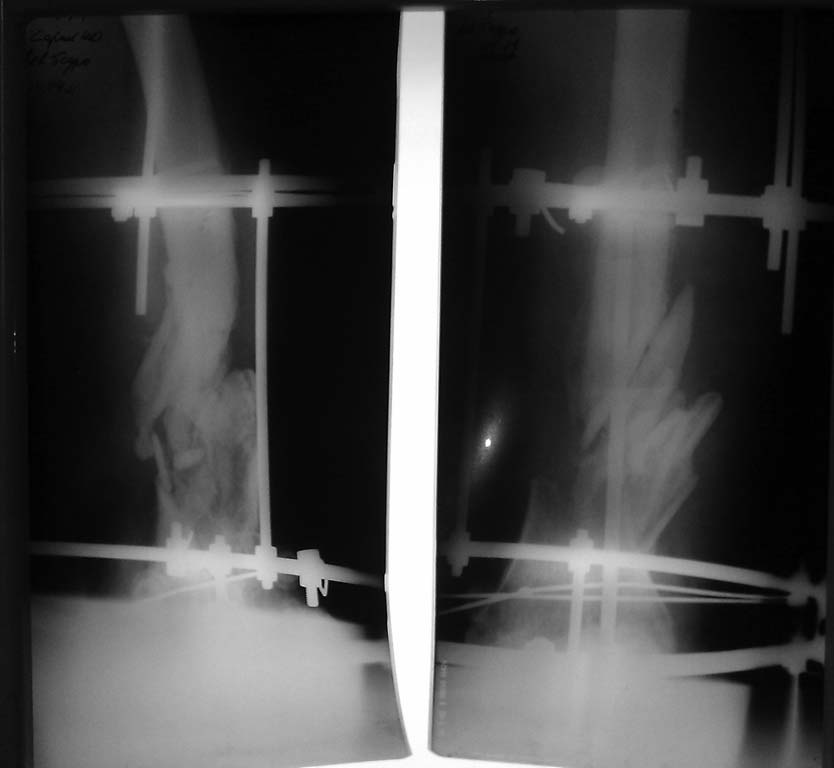

[Ortho] Ложный сустав н/3 бедра

Уважаемые коллеги помогите выбрать метод лечения пациента. Год назад производственная

травма с обширной раной н/3 бедра. Оперирован на Севере спице-стержневым аппаратом. В

настоящий момент рана бедра зажила, аппарат Илизарова снят. Из спицевых ран гнойное

отделяемое. Из области раны отделяемого не было. Как мне мыслится при отсутствии гнойного

процесса открыть место перелома, периостально выделить осколки, произвести

интрамедуллярный остеосинтез ретро-, или антеградным стержнем и жизнеспособные осколки

по возможности уложить в дефект,вокруг штифта.